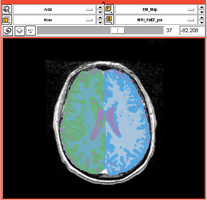

Comprehensive Longitudinal Investigation of Multiple Sclerosis at Brigham and Women’s Hospital (CLIMB) Study

- Collaborator: Svetlana Egorova MD/PhD (Brigham and Women's Hospital(BWH)), Alexander Zaitsev PhD (BWH)

- Short description: Provide Basic EM Segmentation for estimation of brain parenchymal fraction (BPF) . The processing is being performed for the cases with failing PD TDS+ segmentation. The T1-type scans are segmented and registered to PD/T2 images. The requests are being submitted over the Web GUI.

- Image specification: 1.5 Tesla ,Scanner: Varies among participants.

- Used Task: MRI Human Brain Hemisphere